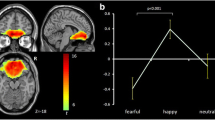

All volumetric images underwent quality control for intersubject homogeneity and visual inspection procedure for potential newly introduced artifacts. Given our interest in the structural covariance of GMVs, only these images were included in our analysis. The total intracranial volume (TIV) was estimated to take into account the variability of brain size. Finally, the GMV of each of the nine bilateral regions of interest (ROIs) drawn from the n30r83 Hammersmith atlas (http://brain-development.org/brain-atlases/adult-brain-maximum-probability-map-hammers-mith-atlas-n30r83-in-mni-space/) was estimated and averaged between the two hemispheres. Given our strong a priori hypothesis, we focused on the brain regions involved in the processing of sad emotions and implicated in FER, according to previous literature: the amygdala, hippocampus, insula, anterior cingulate cortex, orbitofrontal cortex, fusiform gyrus, superior frontal gyrus, medial frontal gyrus, and inferior frontal gyrus (see before, Fig. 1).

Brain regions involved in facial emotion recognition (FER). Gray matter volume was estimated in regions of interest (ROIs) using voxel-based morphometry and averaged across the hemispheres. ROIs drawn from n30r83 Hammersmith atlas are displayed in axial (a, b) and sagittal (c, d) projections of the Montreal Neurological Institute (MNI) template: orbitofrontal cortex (pink), amygdala (dark red), fusiform gyrus (orange), insula (cyan), hippocampus (violet); anterior cingulate cortex (green); superior frontal gyrus (yellow); middle frontal gyrus (light red); inferior frontal gyrus (blue)

FER task

There was an effect of diagnosis on FER-total scores [F(2, 90) = 8.928, p < 0.001], with patients with BD-I having significantly worse performance compared to patients with BD-II and HC (p < 0.001), and there were no differences between patients with BD-II and HC (p = 0.9). In patients with BD-I, the FER-total scores were significantly correlated with the duration of the illness (r = − 0.543, p = 0.02) and the GAF scores (r = 0.656, p = 0.015). The emotion-by-diagnosis ANOVA confirmed the effect of diagnosis (p < 0.001) with the poorest performance in patients with BD-I relative to those with BD-II and HC (all p’s < 0.001), and showed the effect of emotion [F(1, 84) = 31.02, p < 0.001] with the poorest performance for sadness relative to neutral [t(84) = 5.57, p < 0.001], and a marginal significance for their interaction [F(2, 84) = 2.68, p = 0.07] with planned comparisons showing Bonferroni-corrected significance for FER-sadness vs FER-neutral difference comparing patients with BD-I [F(2, 84) = 4.081, p < 0.001] with HC [F(2, 84) = 4.226, p < 0.001] but not with patients with BD-II [F(2, 84) = 1.433, p = 0.156] (see Fig. 2). FER-sadness was significantly correlated with the duration of illness (r = − 0.576, p = 0.012), the GAF score (r = 0.569, p = 0.043), as well as with the number of previous manic episodes (rho = − 0.592, p = 0.012) in patients with BD-I (see Fig. 3). In patients with BD-I, FER-total, and FER for each emotion scores did not correlate with the antidepressant dose or with plasma lithium levels (all p’s > 0.05). Conversely, in patients with BD-I, FER-total, and FER-sadness scores were significantly correlated with the dose of antipsychotics (rho = − 0.561, p = 0.02, and rho = − 0.508, p = 0.04, respectively). We did not find any significant correlation between FER scores and clinical variables in patients with BD-II.

The performance of facial emotion recognition of sadness (FER-sadness) is altered in BD-I relative to BD-II and HC. BD-I and HC show reduced FER during the presentation of sadness compared to neutral, in contrast with BD-II, who have similar performance independent of facial emotion. The colored dots indicate FER performance for each diagnostic group and emotion (sadness in yellow, and neutral in blue); the white dots indicate the mean, and the bars the 95% confidence intervals for each emotion and diagnosis. FER performance scores are calculated as the ratio between the % accuracy and the mean reaction time. BD-I, bipolar disorder type I; BD-II, bipolar disorder type II; HC, healthy controls